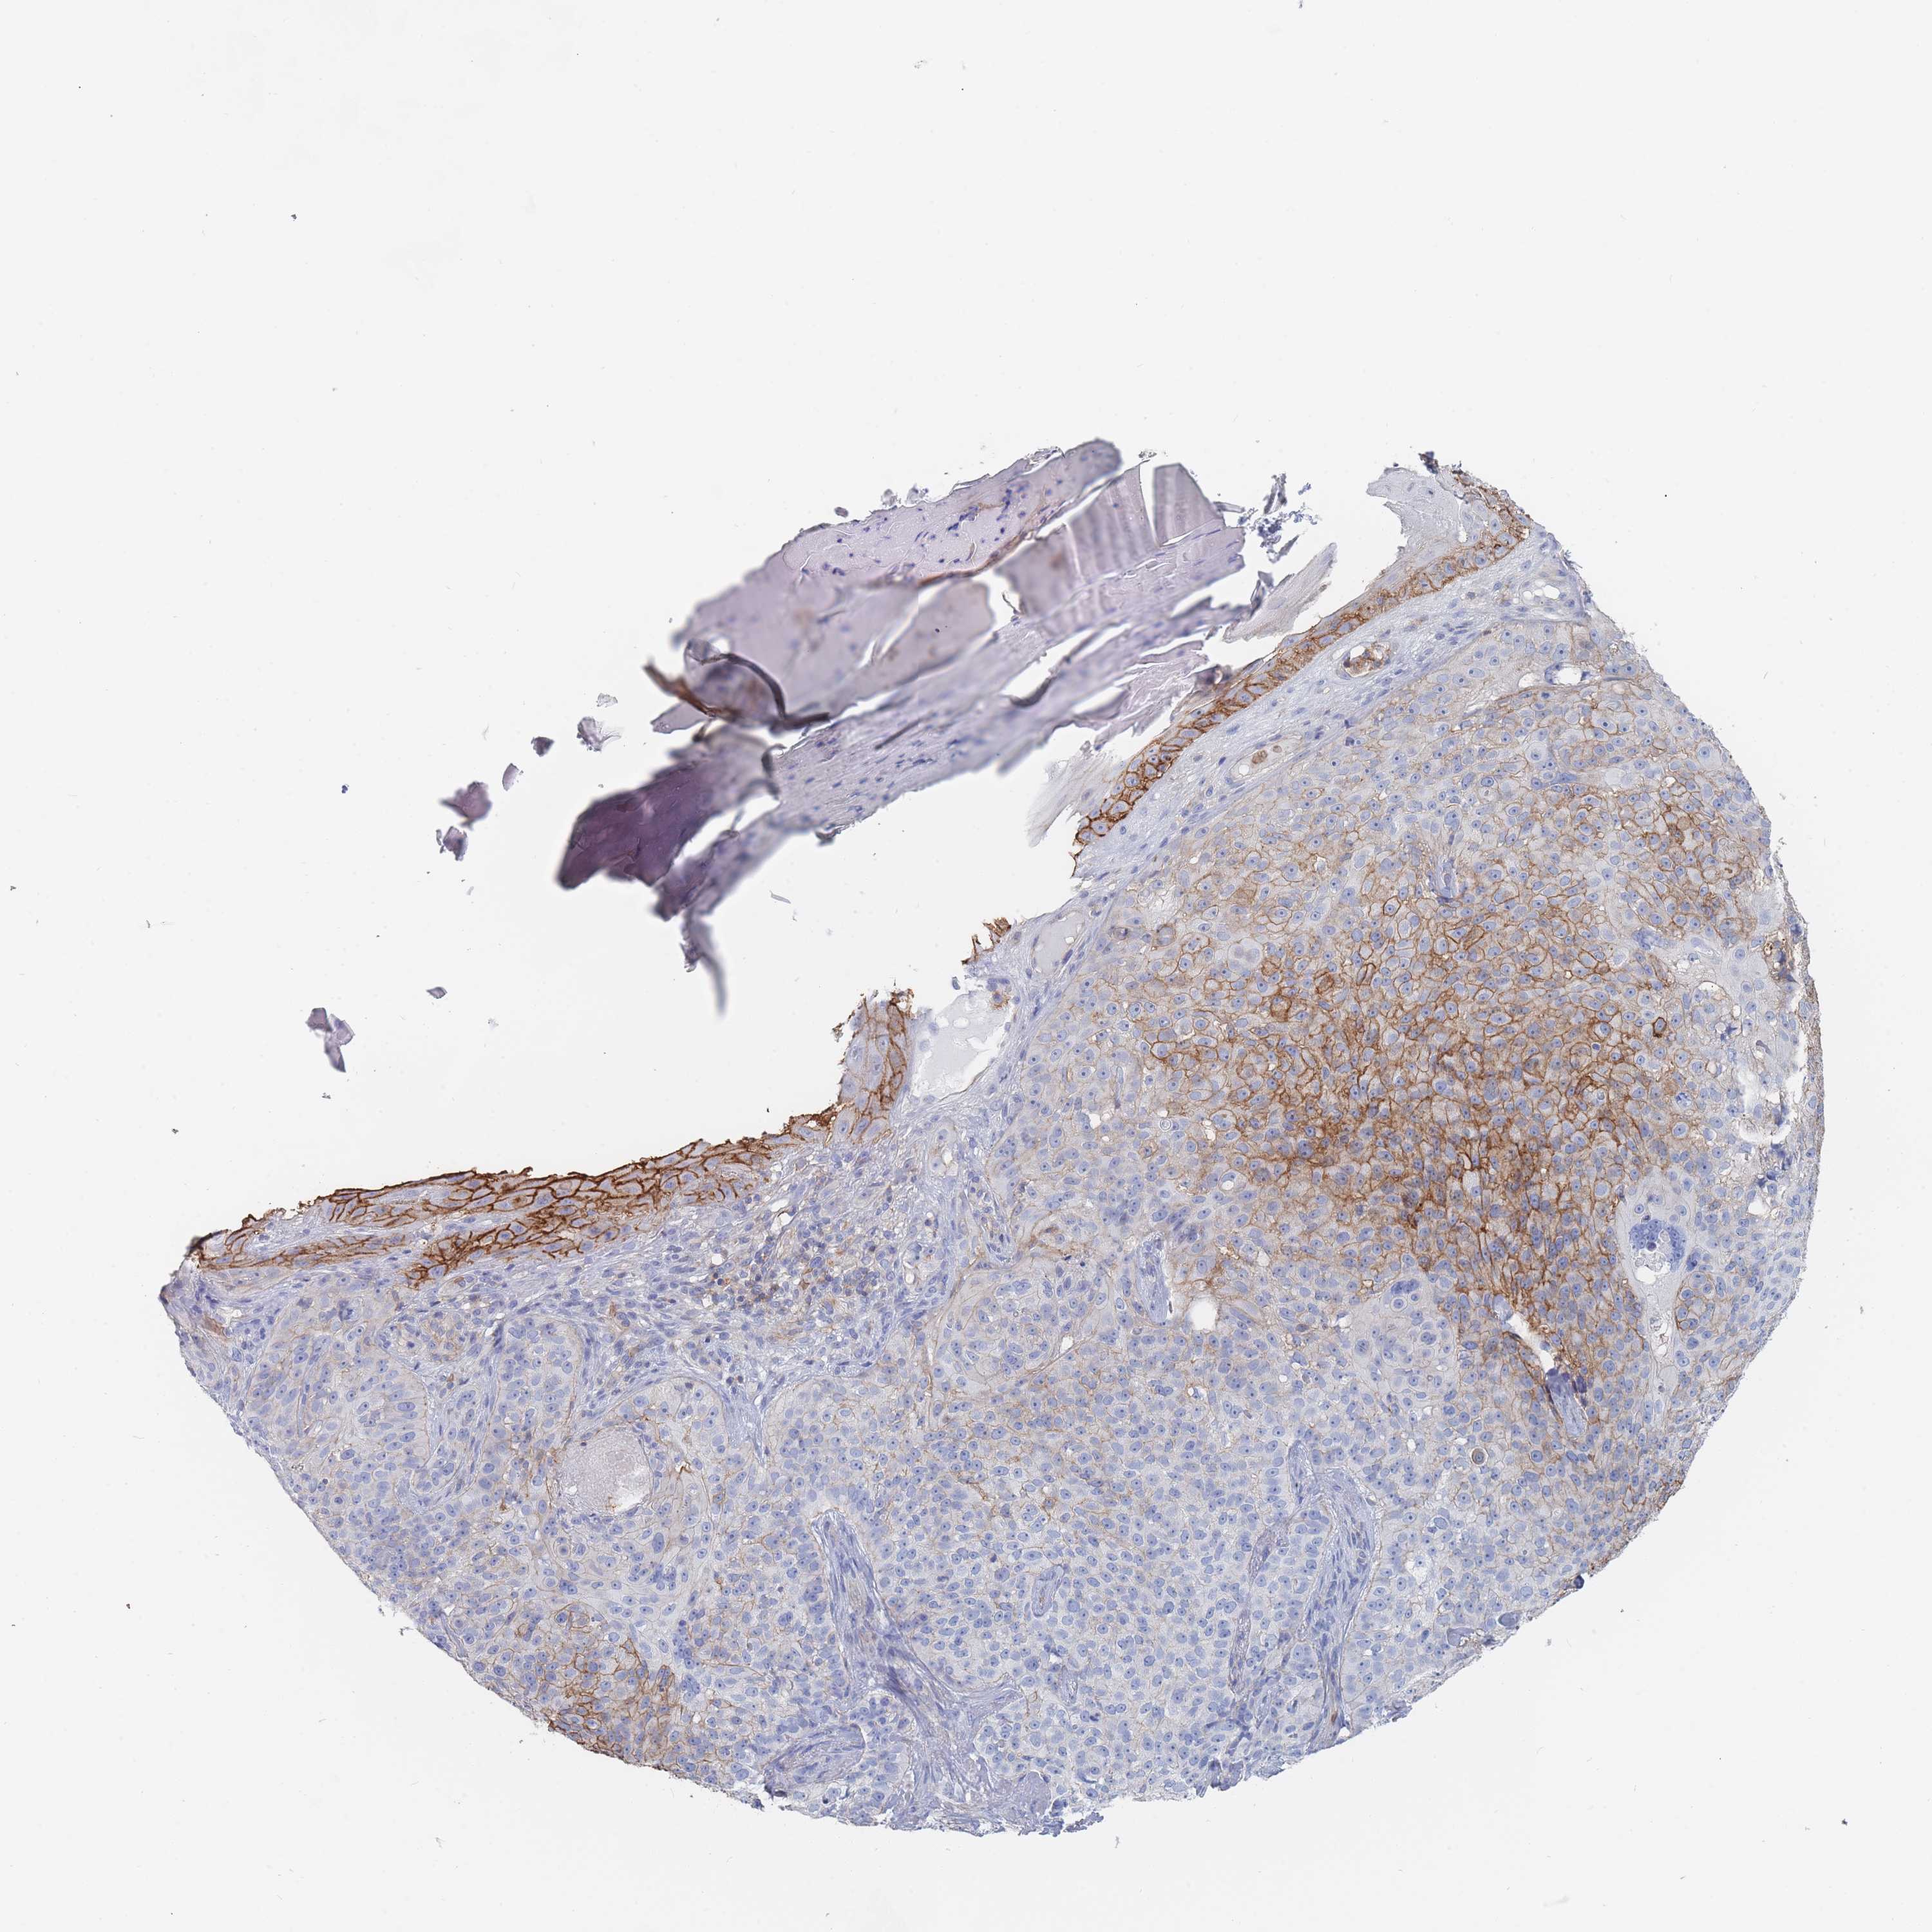

Basal cell and squamous cell cancer

SKIN CANCER - Protein expressioni

A mouse-over function shows sample information and annotation data. Click on an image to view it in a full screen mode. Samples can be filtered based on level of antibody staining by selecting one or several of the following categories: high, medium, low and not detected. The assay and annotation is described here.

Each image is clickable and will lead to virtual microscopy that enables deeper exploration of all samples and also displays staining intensity scores, fraction scores and subcellular localization as well as patient and tissue information for each sample.

Antibody HPA058494

Squamous cell carcinoma, NOS